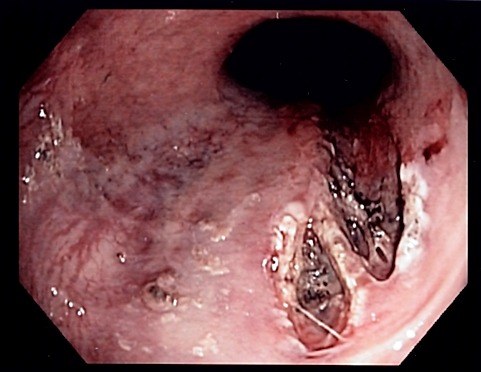

• Эзофагогастроскопия. Введение гибкого эндоскопа через полость рта позволяет оценить состояние эпителиальной мембраны верхних отделов желудочно-кишечного тракта и выявить линейные разрывы, которые обычно расположены в зоне перехода пищевода в желудок. При визуальном осмотре можно определить глубину поражения стенки пищевода или желудка.

• Эндоскопический гемостаз. Если кровотечение продолжается с помощью эндоскопа, поврежденную область прокалывают вазоконстрикторными агентами, вводят склерозирующие агенты, лигируют или отрезают сосуды. Возможна аргоновая плазма или электрокоагуляция.